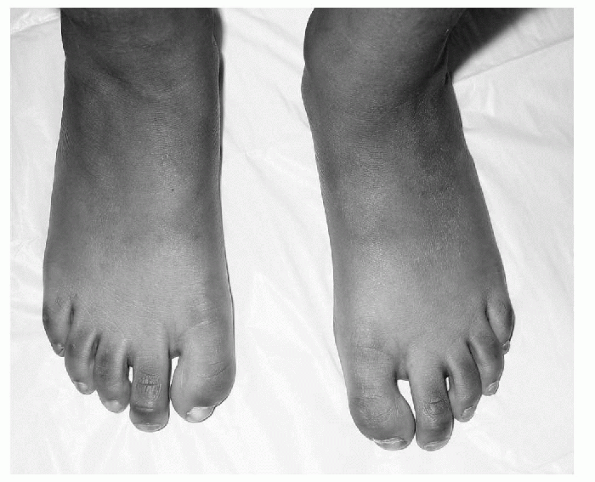

the physical examination. In all cases, a thorough physical exam,

idiopathic clubfoot, positive physical findings include the following (Fig. 4.2-1):

![]() |

Figure 4.2-1 (A) Six-week-old boy with bilateral clubfoot. Note the cavus, adduction, varus, and equinus position of the foot. (B) The arrow indicates a medial crease in the midfoot.